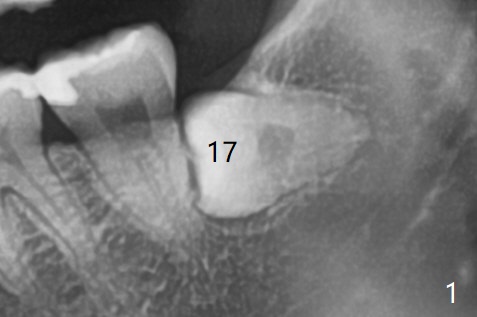

A 27-year-old woman (nervous) is going to return for #16 and 17 extraction (Fig.1).